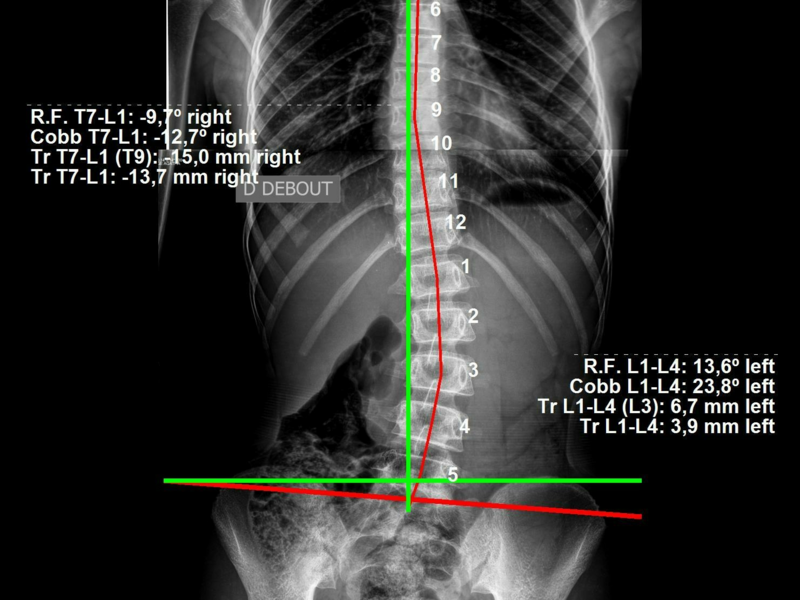

La chirurgie de la scoliose est généralement envisagée lorsque la courbure de la colonne vertébrale devient grave et continue de progresser malgré les traitements non chirurgicaux.

La décision de procéder à une chirurgie dépend de plusieurs facteurs, notamment l’âge du patient, le degré et l’emplacement de la scoliose, la présence de symptômes tels que des douleurs ou des problèmes respiratoires.